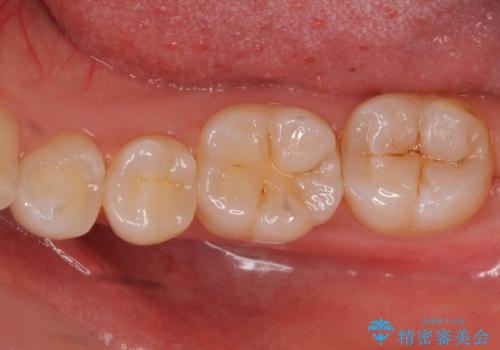

奥歯の虫歯 セラミックインレーによる治療

- 検査をしたところ奥歯に小さな虫歯を発見。

大きくなる前に白い詰め物で治療がしたいとのことでセラミックインレーでの治療になりました。

口の中を見ただけでは異常がないのにレントゲン画像上では虫歯がある、といったことは多々あります。奥歯とはいえ、口をあけると外から見えてしまうため白いセラミックでの治療ができたことを大変喜んでいただけました。